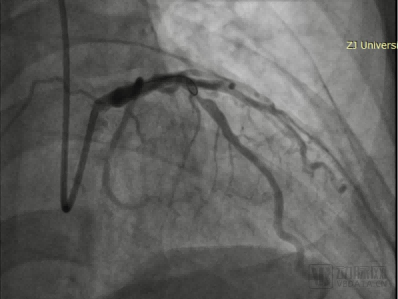

During the surgery, Academician Wang Jian'an's team first used a 3.0 × 13mm spinous process balloon to pre dilate the diseased blood vessel. Subsequently, a 3.5 × 15mm rectangular coronary artery remodeling catheter was used to dilate the blood vessels at 10atm and initiate laser therapy. Postoperative imaging showed good dilation effect, no residual stenosis or dissection, TIMI blood flow level 3, and the surgery was successfully completed.

Postoperative angiography of patients with LAD